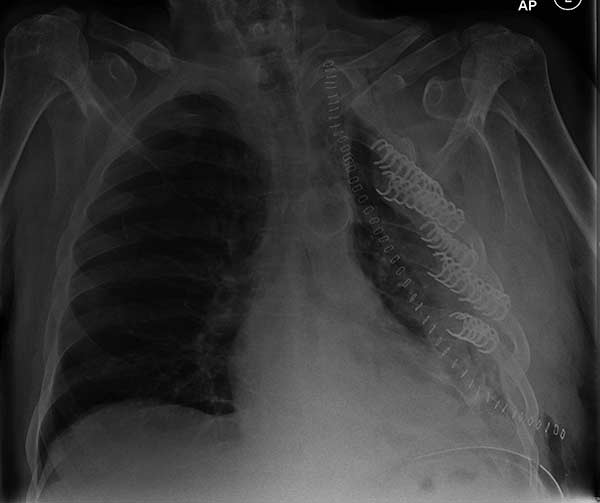

- Chest wall resection for malignancy (Figures 4-5)

![]() |

| Figure 4: Model showing application in chest wall resection. | Figure 5: Postoperative chest x-ray showing the implants |

- Fixation of massive chest wall injury (Figures 9-11)